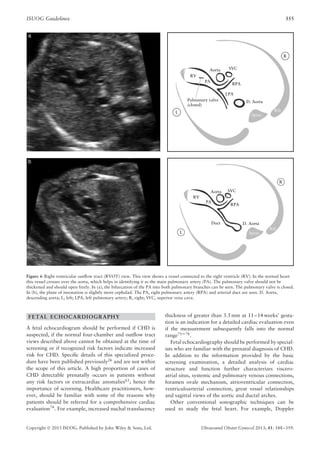

Right ventricular outflow tract (RVOT) view. The

nating from the morphological right ventricle (Figure 6):

Figure 6, the superior vena cava is often seen to the right

by Yoo et al.64.

Figure 6 Right ventricular outflow tract (RVOT) view. This view shows a vessel connected to the right ventricle (RV). In the normal heart

descending aorta; L, left; LPA, left pulmonary artery; R, right; SVC, superior vena cava.